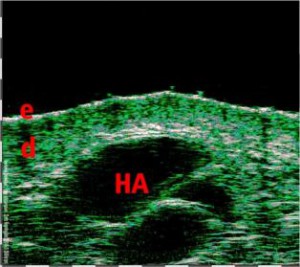

-Υπέρηχος Υψηλής Συχνότητας (HFUS) και Ιστολογία

-Έγχυση Πληρωτικών Υλικών (Fillers)